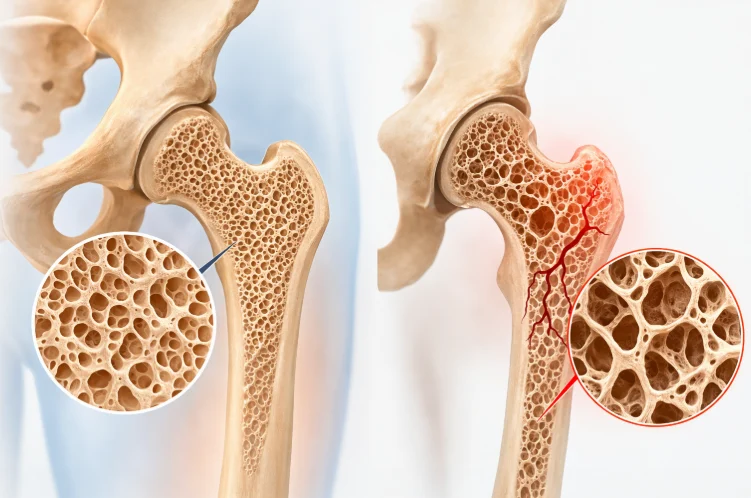

Bone density is an indicator of the amount of minerals in bone, primarily calcium and phosphorus. When this density decreases, the bone structure becomes porous and weaker, making bones more susceptible to fractures even from minor impacts. Maintaining a healthy lifestyle, a balanced diet, and appropriate exercise can help slow bone loss and support natural bone density growth.

Images of healthy bone (left) and osteoporosis (right).